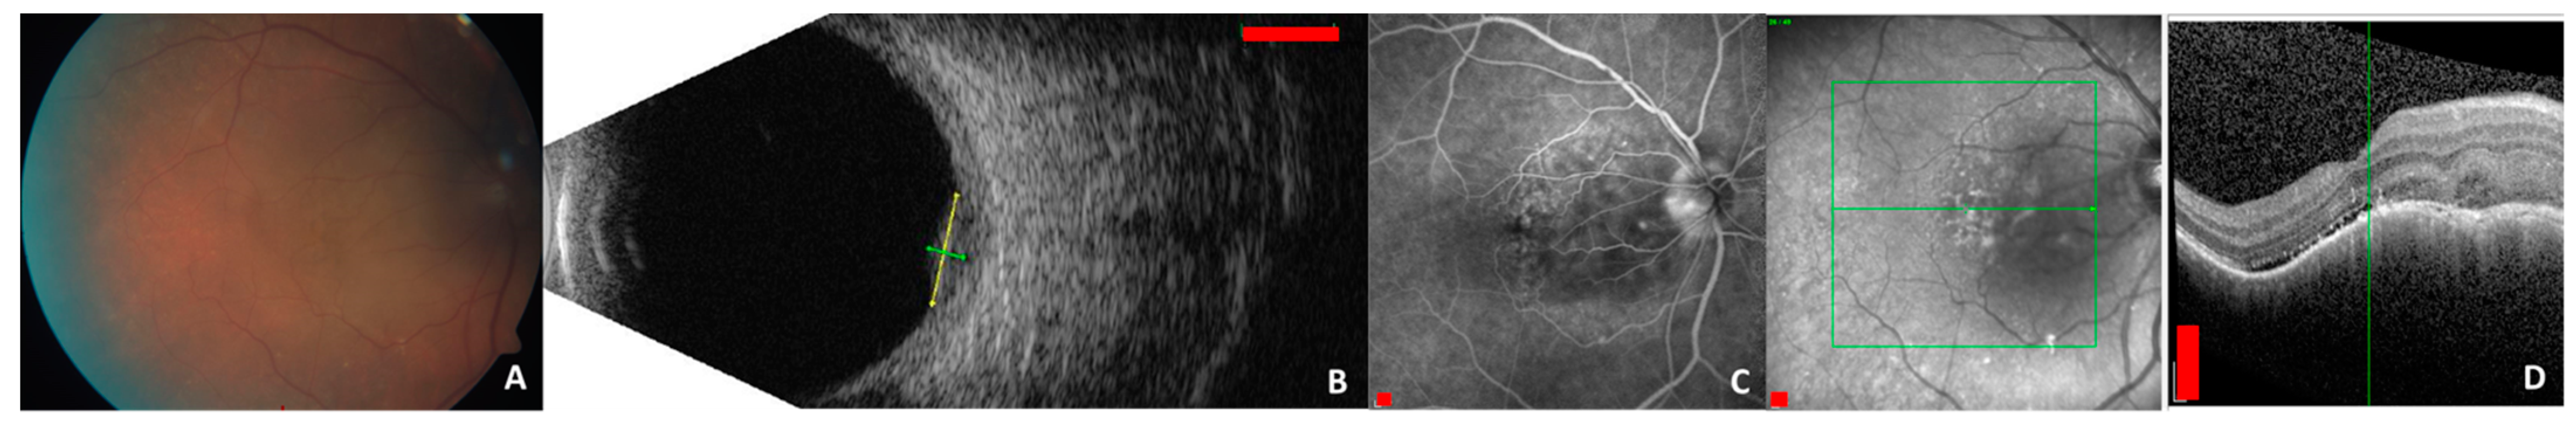

- Sen, M.; Honavar, S.G. Circumscribed choroidal hemangioma: An overview of clinical manifestation, diagnosis and management. Indian J. Ophthalmol. 2019, 67, 1965–1973. [Google Scholar] [CrossRef]

- Shields, C.L.; Honavar, S.G.; Shields, J.A.; Cater, J.; Demirci, H. Circumscribed choroidal hemangioma: Clinical manifestations and factors predictive of visual outcome in 200 consecutive cases. Ophthalmology 2001, 108, 2237–2248. [Google Scholar] [CrossRef]

- Krohn, J.; Rishi, P.; Frøystein, T.; Singh, A.D. Circumscribed choroidal haemangioma: Clinical and topographical features. Br. J. Ophthalmol. 2019, 103, 1448–1452. [Google Scholar] [CrossRef] [PubMed]